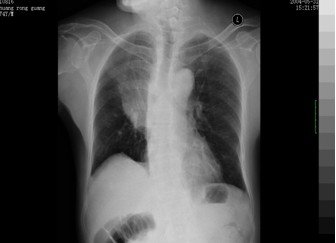

3. 胸部X线检查(下图):

早期:纹理模糊

实变:叶或段分布密度均匀的致密影

完全消散约3周左右

胸片示斑片状或整叶的浸润影

胸部X线检查